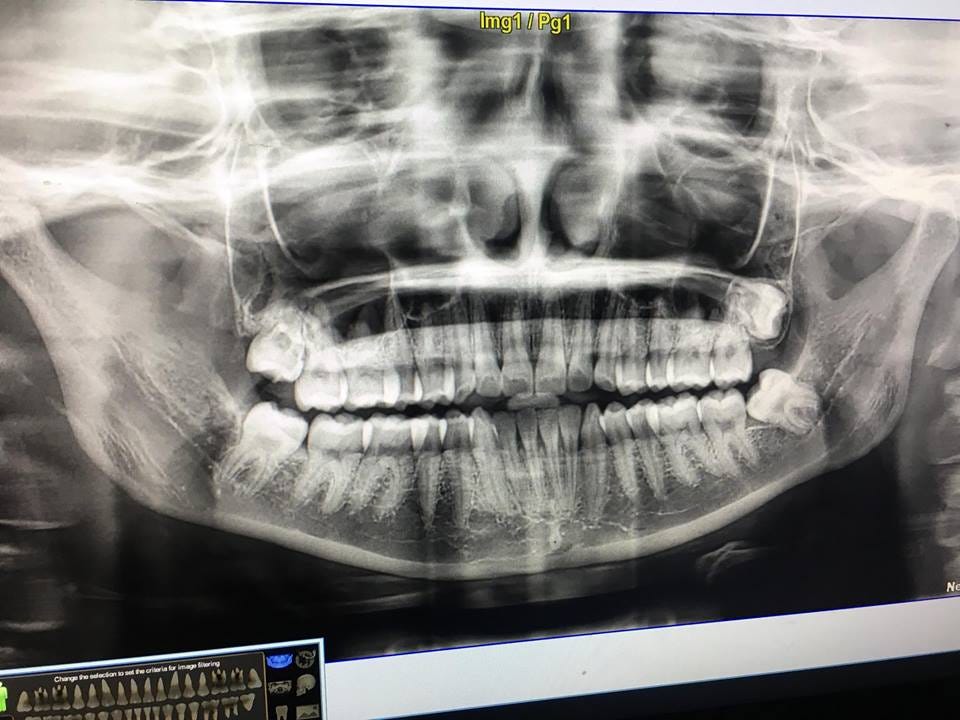

wisdom tooth too close to nerve

What is dental colonectomy? A coronectomy is a dental procedure that is done in certain situations as an alternative to having a . A coronectomy can be done when a dentist feels there is a higher risk of injury to the lower dental nerve. It can also be considered safer than an extraction in people over 40, .Located in the back of your mouth, its third set of molars. They usually come when you're in your last teenage years and they're your last set of adult teeth. For many people, one or more teeth of wisdom do not have enough room to grow properly and break (or eruption) through the gum. These teeth of wisdom are called to be impacted. Often, your dentist will suggest removing—called an extraction—because they tend to be prone to decay and disease. An extraction of standard wisdom teeth will remove all the tooth, and sometimes the four are removed immediately. A coronectomy will remove the crown from the tooth and leave the root of the tooth in the jaw intact. A coronectomy is not recommended if the tooth of wisdom or root is infected. Both procedures can be performed by a dentist or oral surgeon. Your dentist will probably decide a procedure on the other depending on factors such as your age and probability of nerve damage. Sometimes the roots of the teeth of wisdom are close, press, or even wrap around it, the nerves that provide feeling to your tongue, lips and chin. In situations like this, your dentist or oral surgeon might recommend a coronectomy as an option that could reduce the risk of potential nerve damage compared to an extraction. Damage to your NL and NAN may result in:According to a , extracting a tooth of wisdom with roots near the NAD can cause direct or indirect damage to the nerve. Coronectomy in this situation may be a safe procedure associated with a low incidence of injury in the lingual or lower alveolar nerves. According to others, a coronectomy is preferable to extraction to prevent neurological damage when the roots are near the IAN. According to one, a small percentage of people who have had a coronectomy will have erupt roots and then need to be removed. Although rare, in these cases extraction is no longer a problem because the roots have grown far from the IAN. A suggests that coronectomy is a safer option for people over 40 years of age because they have a higher risk of nervous damage. A coronectomy is not commonly recommended for young people who need a tooth of wisdom removed because the root of the tooth is not fully formed. Younger people also tend to heal faster and better than older individuals. After your coronectomy, you will probably have some swelling and discomfort, although usually less than what you would do after a complete extraction. Your dentist will provide post-care instructions and may prescribe antibiotics, even if the risks of and are reduced compared to extraction. As with any dental procedure, if you notice any signs of infection, excessive bleeding or other unusual symptoms, you should call your dentist or oral surgeon. Typically a coronectomy is used when the tooth that needs to be removed has roots that are close to important nerves. There are specific situations when a coronectomy is usually not recommended, such as:If you have impacted the teeth of wisdom, your dentist or oral surgeon will perform a physical exam of your mouth and consult the dental X-rays. They will then make recommendations on the best course of action, including surgical options. The typical surgical option is a complete extraction of the tooth (or teeth), but it can also be a coronectomy in which the tooth crown is removed but the roots are left in place. A coronectomy is often recommended when the root of the tooth is close to important nerves, to avoid nervous damage. Talk to your doctor about the best procedure for you. Last medical review on July 18, 2019Read this following